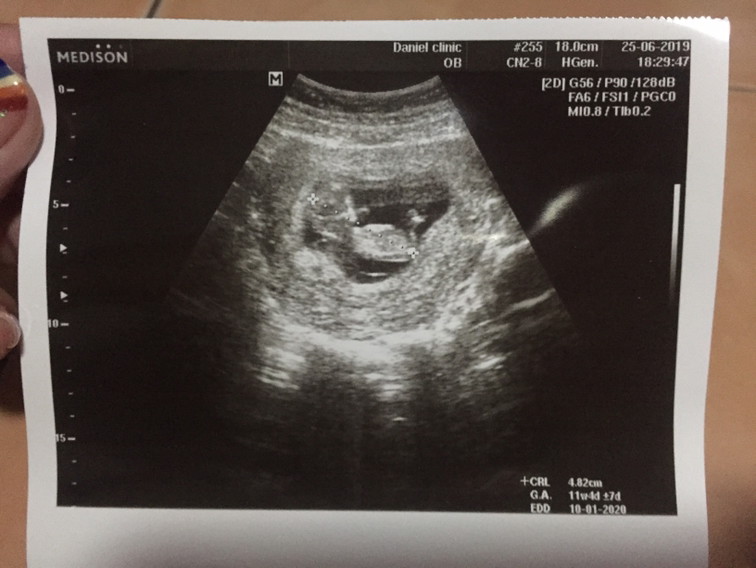

11w6วัน

11 wค่ะ